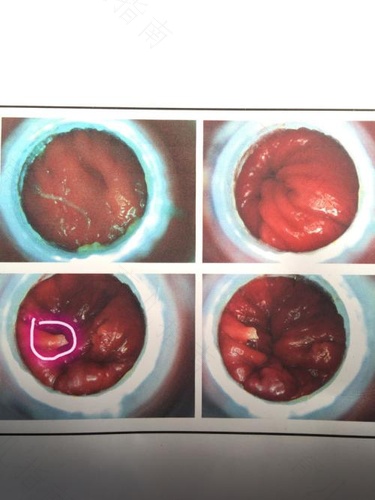

乳头息肉发生恶变的概率是比较小的,一般要是息肉比较小也不多,且无疼痛糜烂等症状出现的话,那就不用进行特殊治疗。但要是息肉不断变大,那就要及时去医院检查,排除恶性肿瘤的可能性,必要时可能还需要通过手术切除息肉,防止引起其他并发症。